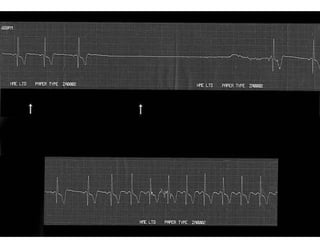

Respuesta presincopal Cardioinhibitoria en el Síncope  Neurocardiogénico. El ECG muestra el dramático enlentecimiento de la FC desde 95 lat/min a 40 lat/min justo antes que se produzca el síncope.

Hipersensibilidad de Seno Carotideo  Efecto Cardioinhibitorio  Este ECG muestra 10 segundos de paro  ventricular siguiendo al masaje de seno carotideo. Las 2 flechas muestran el periodo de masaje. La implantación de un marcapaso permanente abolió los sintomas del paciente.

Respuesta presincopal Cardioinhibitoriaen el Síncope Neurocardiogénico. El ECG muestra el dramático enlentecimiento de la FC desde 95 lat/min a 40 lat/min justo antes que se produzca el síncope.

Hipersensibilidad de SenoCarotideo Efecto Cardioinhibitorio Este ECG muestra 10 segundos de paro ventricular siguiendo al masaje de seno carotideo. Las 2 flechas muestran el periodo de masaje. La implantación de un marcapaso permanente abolió los sintomas del paciente.